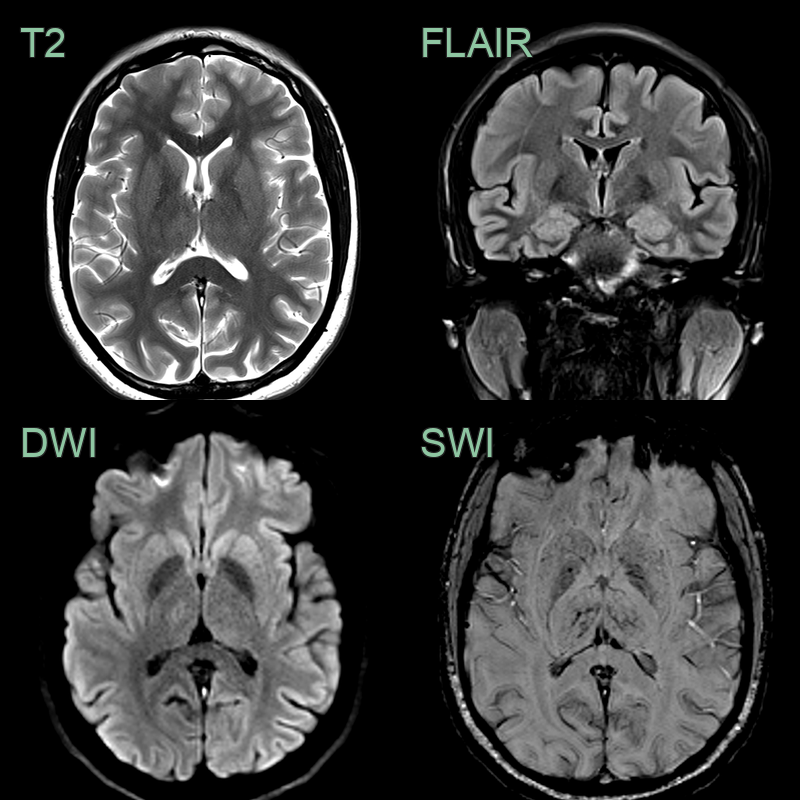

- 30-year-old patient presented with headache, confusion and expressive dysphasia.

- CT showed subtle hypodensity in the deep grey nuclei and hyperdensity within the straight sinus, vein of Galen, and internal cerebral veins. These structures were occluded on both the CTA and phase-contrast MRV.

- MRI showed hyperintensity and diffusion restriction in the deep grey nuclei. SWI showed congenstion of the deep venous system.

- 2 weeks later, a repeat MRI showed only very minimal hyperintensity in the thalami (where some microhaemorrhages had developed) indicating that the diffusion restriction was largely reversible although a few microhaemorrhages developed in the thalami.